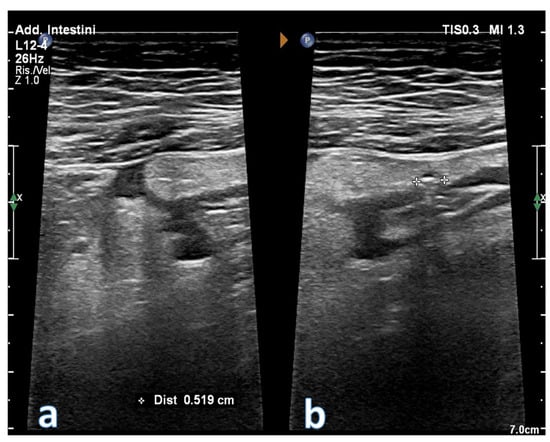

2. Ultrasonographic Anatomy of Gastrointestinal Tract